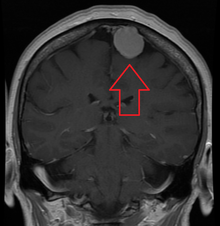

Meningiomas are visualized readily with contrast CT, MRI with gadolinium,[14] and arteriography, all attributed to the fact that meningiomas are extra-axial and vascularized. CSF protein usually is elevated if lumbar puncture is attempted.